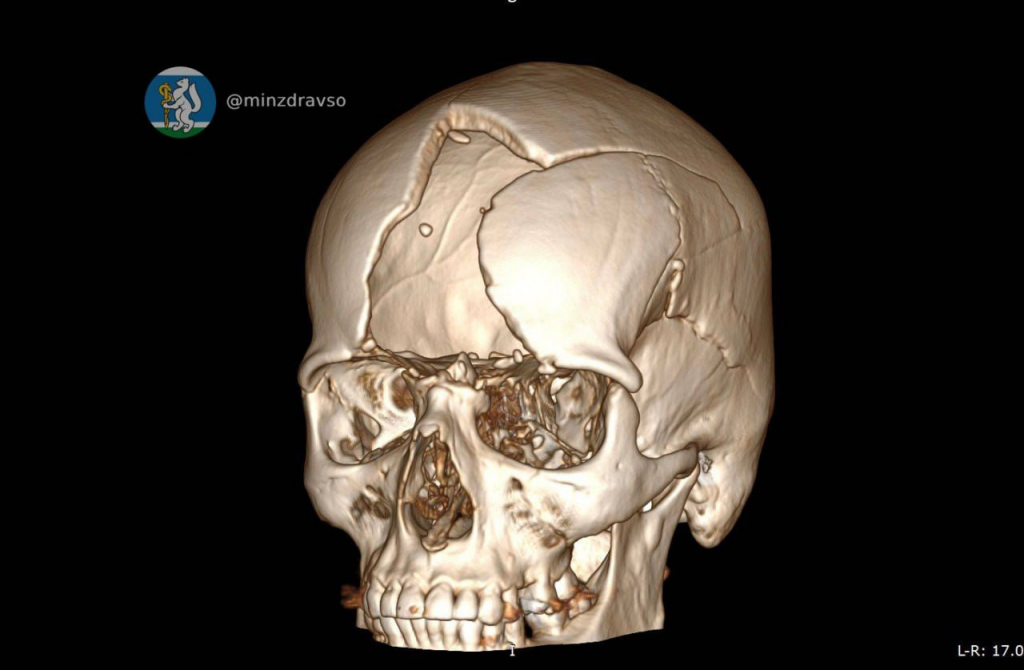

Специалисты провели 3D-моделирование черепа, воссоздали виртуальный прототип анатомической формы, а затем в лаборатории 3D-технологий госпиталя изготовили индивидуальную танталово-титановую пластину, точно соответствующую объёму и контуру разрушенного участка.

«Данная технология позволила сократить время хирургического вмешательства в два раза и не подвергать пациента воздействию препаратов для наркоза, пока хирург моделирует пластину», — отметил нейрохирург Александр Кашин, проводивший оперативное лечение.

Реконструкция выполнена в условиях полной стерильности, с точной посадкой импланта и последующим восстановлением целостности твёрдой мозговой оболочки и мягких тканей. Пациент перенёс вмешательство удовлетворительно, состояние стабилизировалось, наблюдается положительная динамика. Несмотря на тяжесть ранения и сложный путь лечения, мужчина включён в раннюю реабилитационную программу.